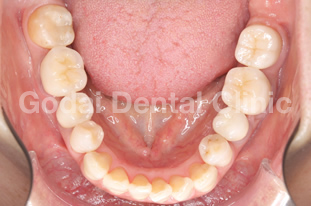

患者様は40代女性で、歯の痛みを理由に来院されました。育児を行いながら仕事をされている方で、毎日が忙しくなかなか歯科へ通う時間がなかったそうです。育児と仕事の空き時間を利用し、できるだけ通院が負担にならないよう、むし歯治療の計画を立てました。金属アレルギーがあることと、見た目もきれいにしたいという希望があったため、被せ物はオールセラミックスによる治療を選択し、小さいむし歯はコンポジットレジンによる詰め物で対応しました。限られた時間の中での通院でしたが、患者様と共に計画を立て治療を進めていくことで、最終的にとても満足していただくことができました。

術後上顎

術後下顎